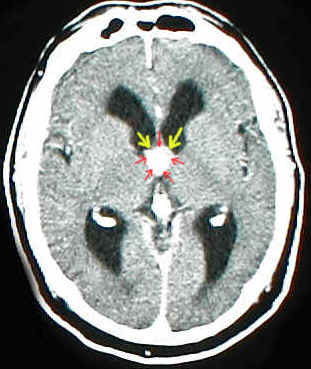

Das Bild zeigt einen Okklusionshydrocephalus: eine gutartige Geschwulst (Kolloidzyste) behindert den Liquorabfluß aus den Seitenventrikeln in den III.Ventrikel. Die roten Pfeile zeigen den Tumor, die gelben Pfeile deuten an, wo der Liquor eigentlich durchfließen sollte, nämlich durch die For. Monroi, die aber durch den Tumor verlegt sind.